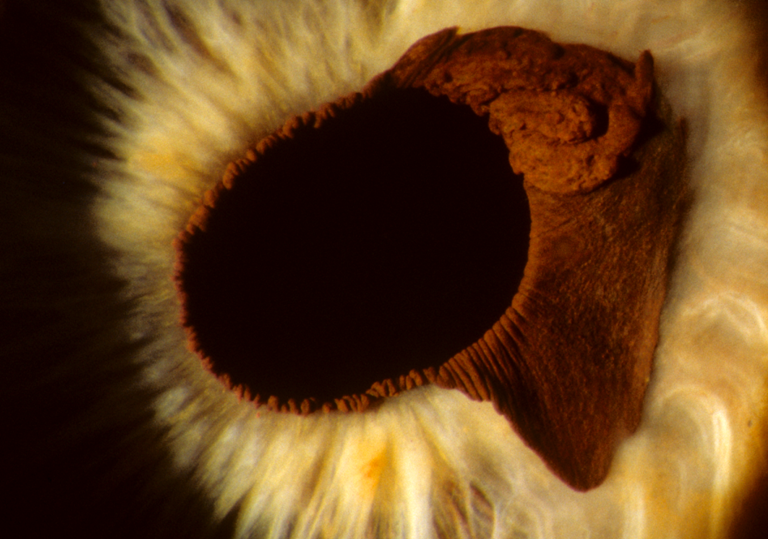

Ectropic Iris

Presented by Denice Barsness, BA, CRA, COMT, ROUBThis photograph received 1st Place in the category "Slit Lamp Photography" and was displayed at the 2024 ASCRS/OPS Society Exhibit.